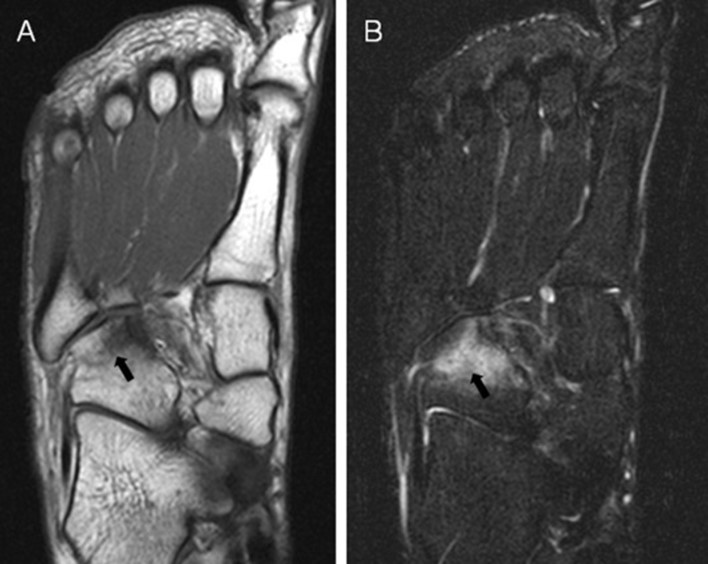

MRI image of increased signal (white areas) on the cuboid bone, which indicates a stress fracture. Contributed by Asia Pacific Journal of Sports Medicine.